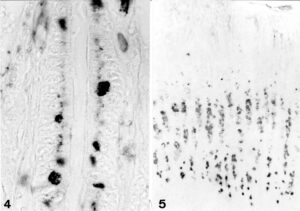

Dolichos biflorus (DBA and Arachis hypogaea (PNA) binding in gastric mucosa. DBA in surface epithelial cells (upper left) and in parietal cells (bottom left). Gastric carcinoma of the diffuse type with PNA binding tumor cells besides non reacting tumor cells (right)